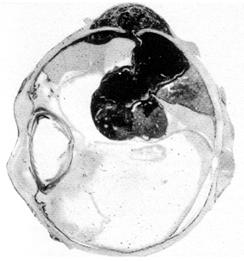

stadiul de invadare orbitara apare cand tumora perforeaza globul si invadeaza tesuturile invecinate (Fig. 12.5);

Fig. 12.5 -

Melanom coroidian std III

- examenul histopatologic stabileste tipul tumorii (Fig. 12.7).

Fig. 12.6 -

Melanom coroidian - aspect clinic

Fig. 12.7 - Melanom coroidian - aspect histopatologic